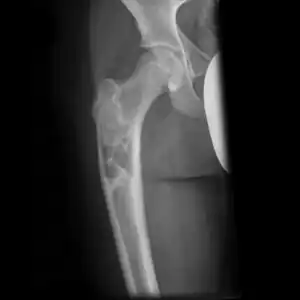

| X-ray: Simple bone cyst in left upper arm of 13 year old | |

Multloculated cavity in the long bone of the thigh, near the hip.